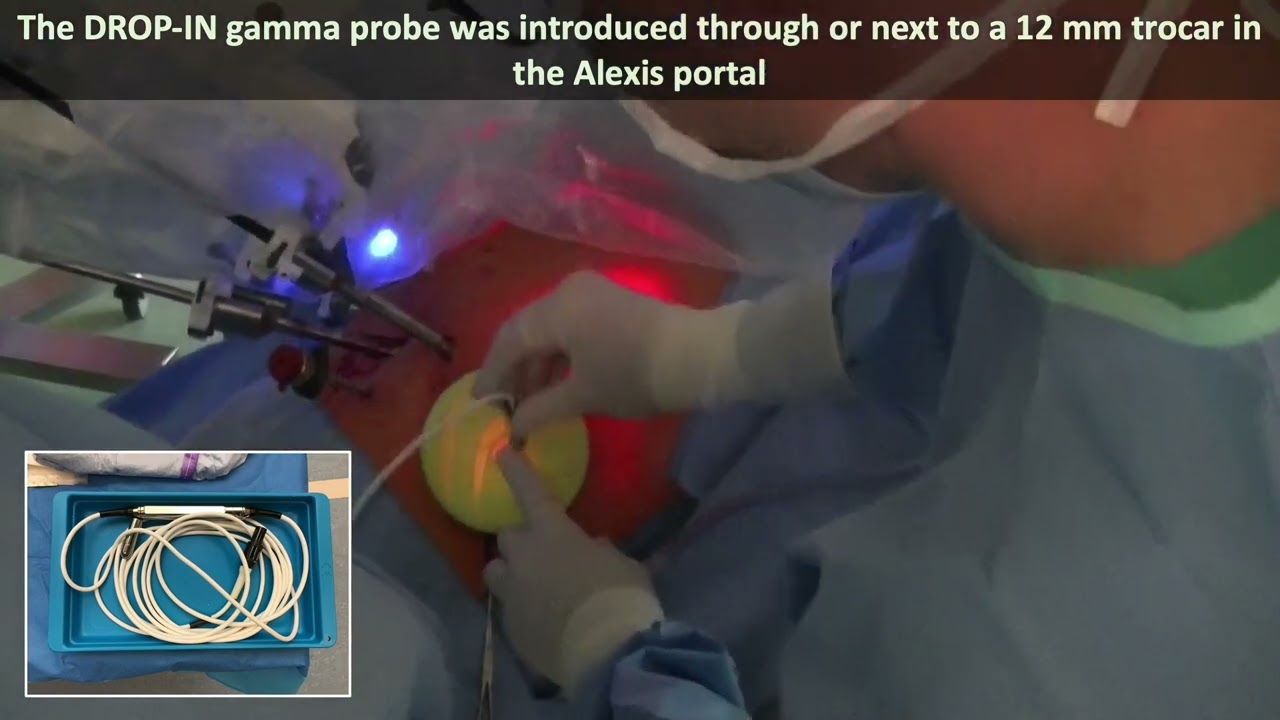

Robot-assisted radioguided surgery using a DROP-IN gamma probe